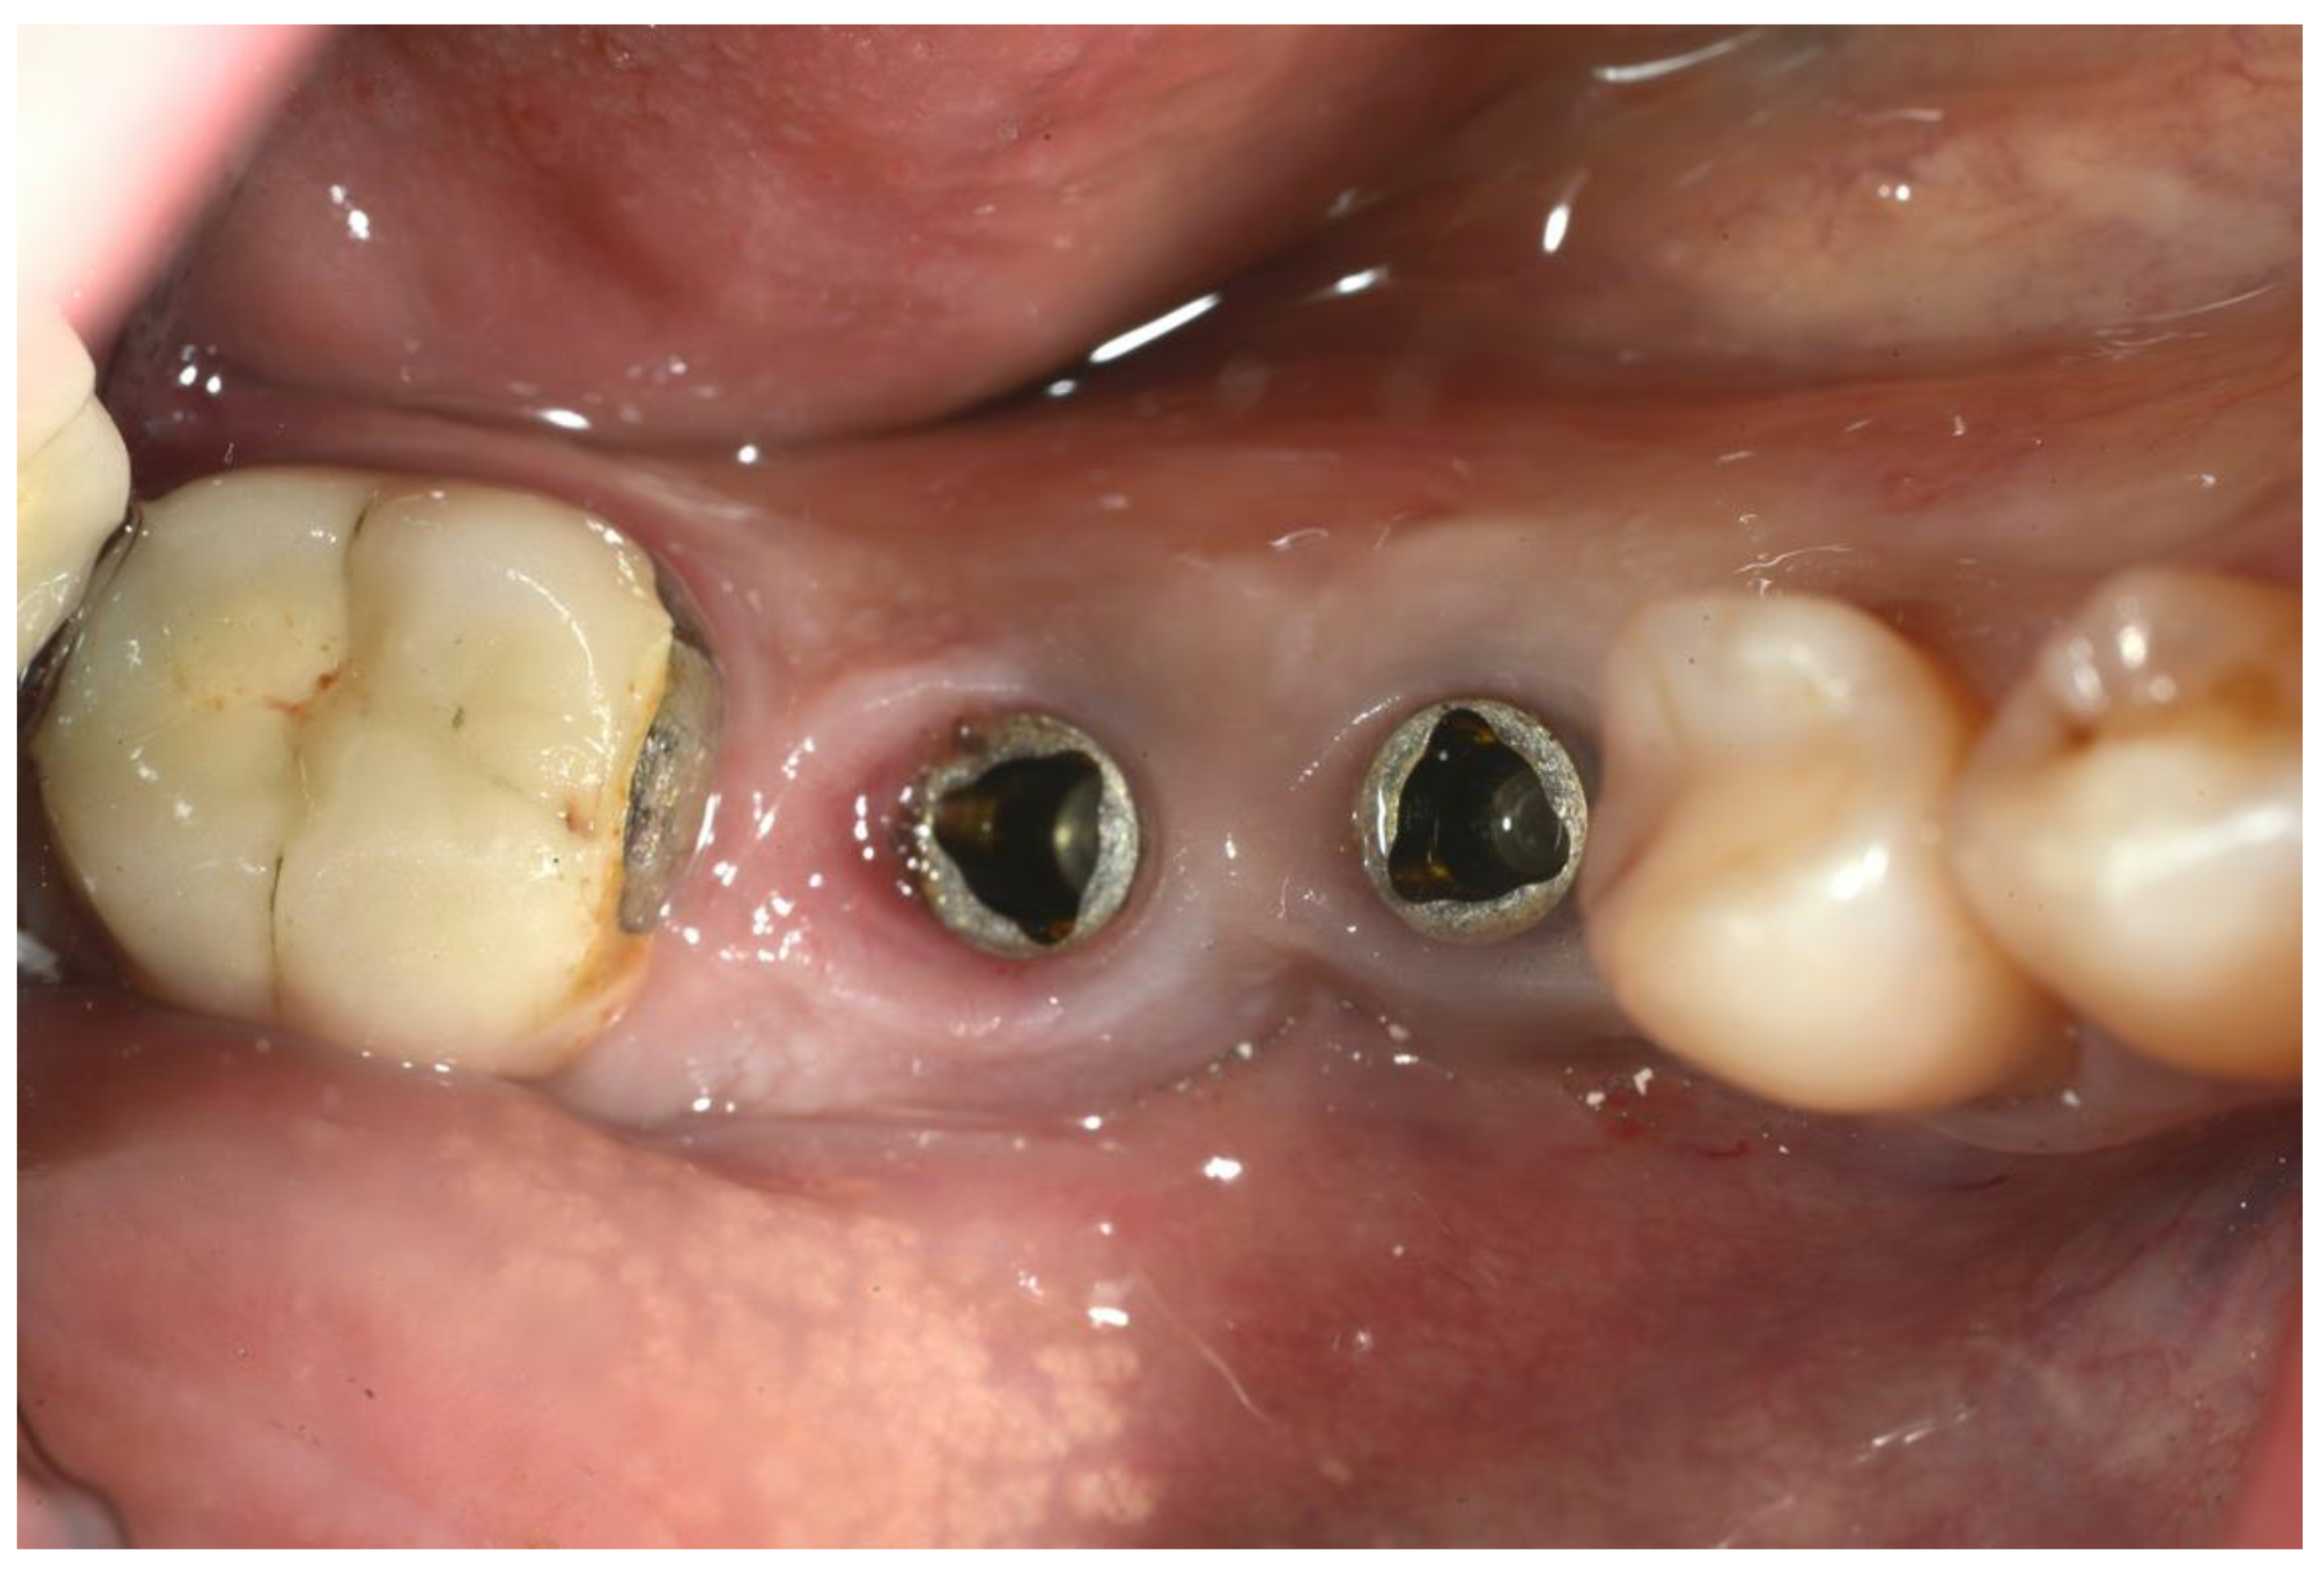

2. Materials and Methods

3. Results